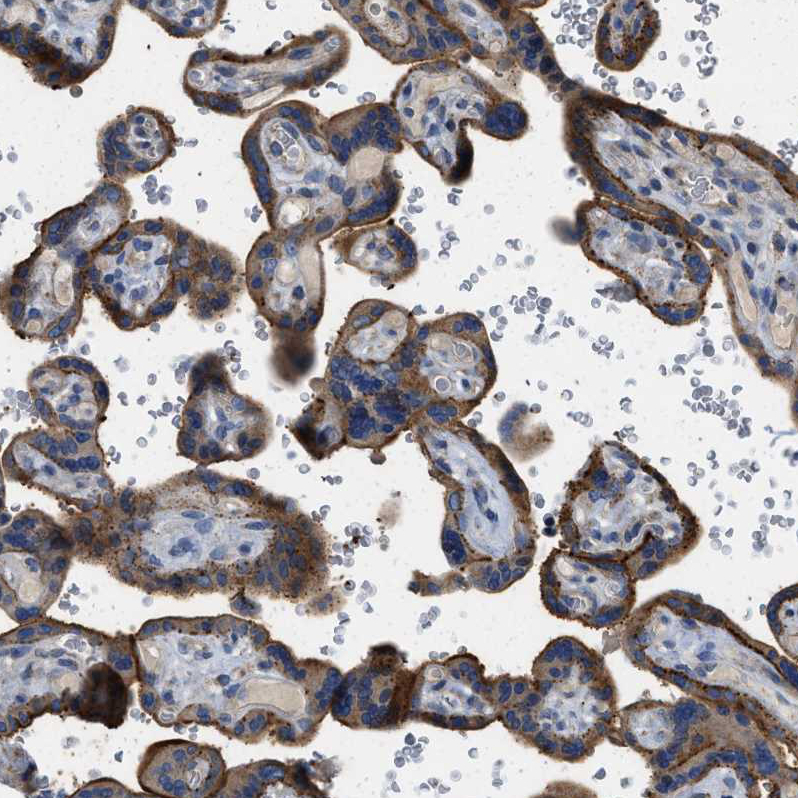

Immunohistochemical staining of human placenta shows strong granular cytoplasmic positivity in trophoblastic cells.